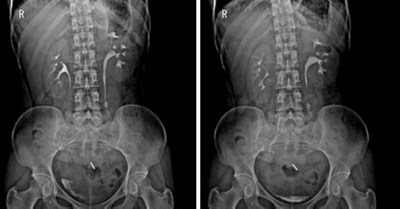

★適用于全身各部位攝影,包括常規攝影(立位攝影、臥位攝影等,如胸片、頸椎、腰椎、腹部、頭顱、四肢等)和特殊攝影(傾斜攝影、角度攝影等,如瓦氏位、骶髂關節、髕骨軸位、跟骨軸位等)。